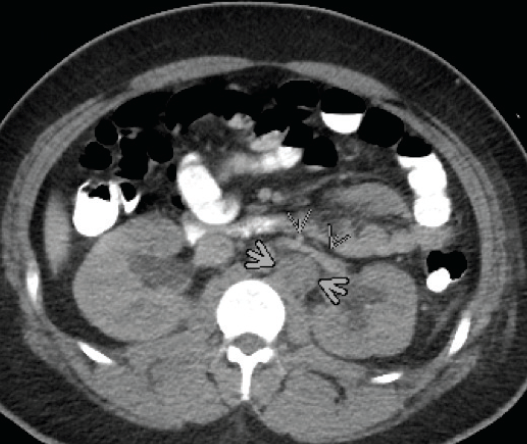

Figure 1. Axial computed tomography image, at the level of the renal veins, showing a large metastatic retroperitoneal lymph node (large arrowheads) displacing the left renal vein anteriorly (small arrowheads).

Computed tomography (CT) scans (Figure 1) revealed a retroperitoneal mass infiltrating the genitourinary system, causing external compression of the left ureter and displacing and partially encasing the aorta and inferior vena cava. CT scans also revealed a large metastatic retroperitoneal lymph node displacing the left renal vein anteriorly (Figure 2).